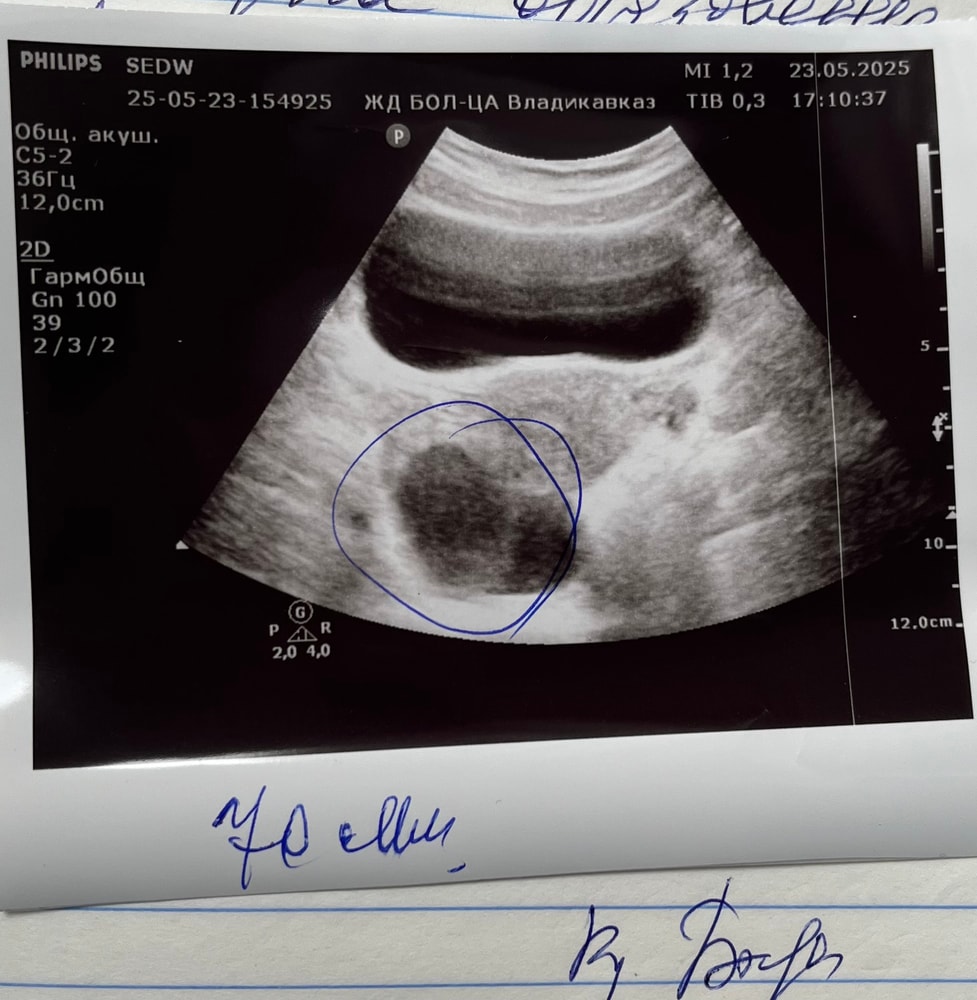

Двухкамерная киста в правом яичнике

Чудо 39, ничего не сказали